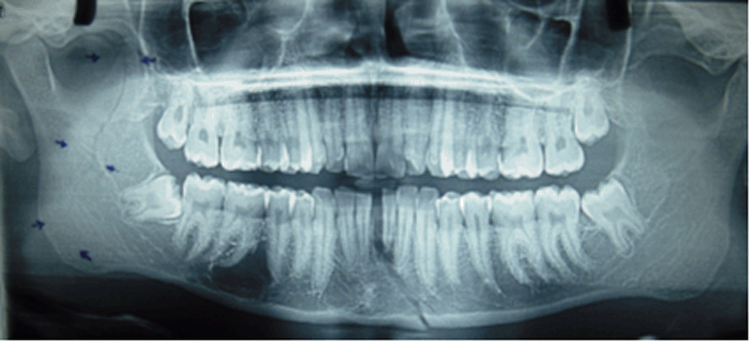

A 21-years-old male patient reported with the chief complaint of pain in the left temporo-mandibular joint (TMJ) region and difficulty in mastication since six days. He had sustained a blow by the elbow on the right angle of the mandible during the inter-university football match. Clinical examination revealed, moderate swelling over the right angle of the mandible and right TMJ region extra-orally with adequate mouth opening. The TMJ movements were normal including lateral excursive movements. There was no step defect in the right angle or ramus of mandible. Intra-orally occlusion was de-aranged on right side with 2–4 mm open bite in the premolar-molar region with ecchymosis in the right retromolar region. Incomplete fracture of the ramus was suspected. Radiological examination (orthopantomogram) revealed a sharply defined radiolucent line extending from the apex of the right coronoid process of the mandible to the mandibular foramen, where a slight deviation was identified, and then extending inferiorly to the angle of the mandible in (Figure 1). There was another fracture in the symphysis region with the fracture line extending from the apices of the right mandibular central and lateral incisors to the inferior border of the mandible. The diagnosis of fracture right coronoid process with minimal displacement along with fracture in the left parasymphysis region was made. Under nasoendotracheal intubation Erich arch bar fixation was done in maxillary and mandibular dental arches. The fractures were reduced by taking patient's occlusion as a guide. The inter-maxillary fixation was done. Satisfactory pre-injury occlusion was achieved. The maxillo-mandibular fixation was kept for three weeks. The patient was followed up for six months post operatively without any esthetic or functional problems.

Figure 1: Orthopantomogram showing longitudinal fracture of coronoid process.